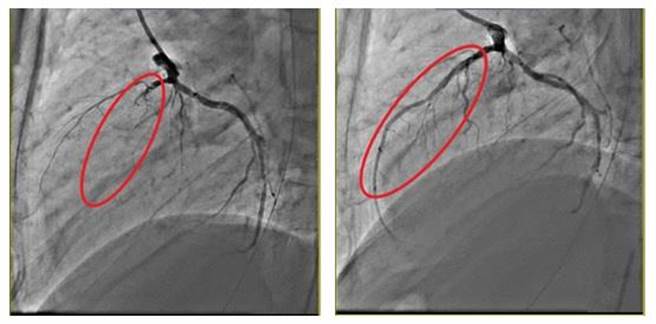

患者冠状动脉的左前降支完全阻塞,看不见血管(左红圈处);装置血管内支架后,血流恢復畅通(右红圈处)。(澄清医院提供/冯惠宜台中传真)

刘昱成表示,该患者送急诊抢救后救回心跳并插管,从心电图显示是急性心肌梗塞,左前降支已有90%阻塞,突发性血栓塞将原本狭隘的血管塞住,经紧急做心导管手术先将小小血栓抽出,再用血管内气球扩张狭窄的血管并装置血管内支架,血流恢復畅通后血压和心跳恢復稳定,稍后意识恢復但仍在加护病房住院数日后续观察。